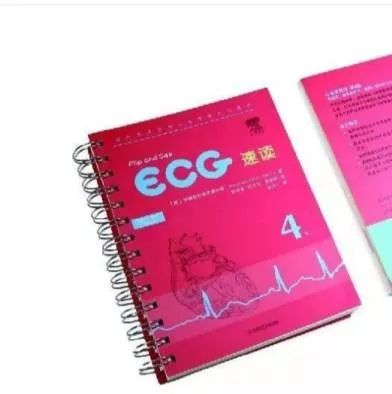

畅销便携的心电图入门工具书,送给自己最好的礼物~ 医学界影像诊断与介入频道 · 公众号 · 医学 · 7 年前 · |